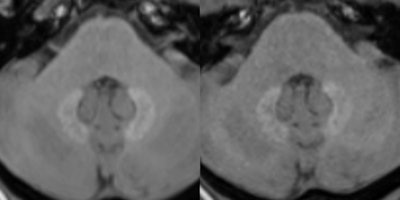

Unenhanced T1-weighted MR images at 3 tesla depict a patient with pre-existing hyperintensities in the dentate nucleus. The left image displays the cerebellum prior and the right image after five serial injections of the macrocyclic GBCA Gadavist. A subtle decrease of the pre-existing hyperintensities can be noted. Images are courtesy of Dr. Alexander Radbruch.

Unenhanced T1-weighted MR images at 3 tesla depict a patient with pre-existing hyperintensities in the dentate nucleus. The left image displays the cerebellum prior and the right image after five serial injections of the macrocyclic GBCA Gadavist. A subtle decrease of the pre-existing hyperintensities can be noted. Images are courtesy of Dr. Alexander Radbruch.The researchers speculated on four reasons for the decrease in signal intensity of pre-existing hyperintensities. Radbruch said the potential signal intensity decrease is most likely not connected with the injection of macrocyclic GBCAs, but it might be explained by a washout of the gadolinium, precipitation of the gadolinium over time, or a combination of both mechanisms. In addition, some gadolinium may have been eliminated through excess ligands, or the decrease may be due to a signal increase in the pons, which could have affected the ratios.